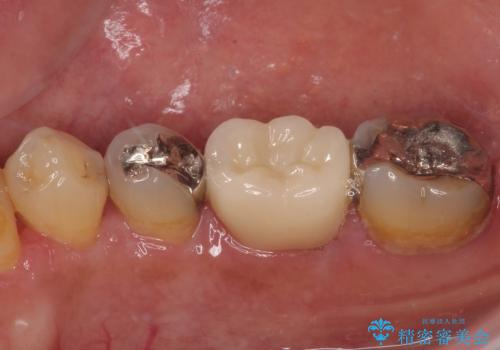

- 銀歯を外して虫歯治療をしたいとのことで来院された患者様です。右下の7番目の歯は銀歯の下に虫歯が広がっており根管治療の可能性もあることを説明したうえで治療を行いました。

左下の5番目の歯はセラミックインレー修復で治療を行うことにしました。

左下の7番目の歯は仮歯に置き換えた後自発痛、咬合痛の所見を認めたので、当院院長である藤巻先生に担当してもらっています。